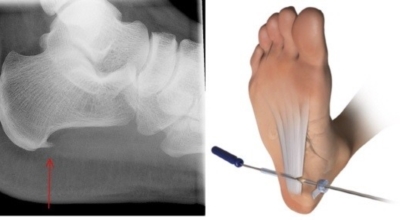

비수술적 치료 방법에으로 보조기, 체외충격파, 스트레칭, 스테로이드 주사요법, 비스테로이드성 소염진통제 등이 여러 방법들이 있어요. 족저근막염 발생초기에는 스트레칭을하여 족저근막 또는 아킬레스건을 효과적으로 증가시키는 것만으로 추가적인 피해를 방지할 수 있죠. 그리고 보조기를 착용해서 뒤꿈치에 가해지는 충격을 완화 시킬 수 있어요. 발에 부종이 생긴 경우 진통주사를 이용해서 치료할 수 있어요. 수술적 치료로 들어가기 전 체외충격파를 이용해서 증상완화의 효과를 볼 수 있다고 해요.

최근 관절경을 이용해서 족저 근막 절개술을 시도하기도 하는데 수술적 치료의 성공률은 70~90%로 높게 알려져 있어요. 하지만 수술 후 신경 손상 과 같은 합병증이 유발될 수 있기 때문에 잘 알아보고 전문의와 상담후 수술을 결정하시는게 좋아요.